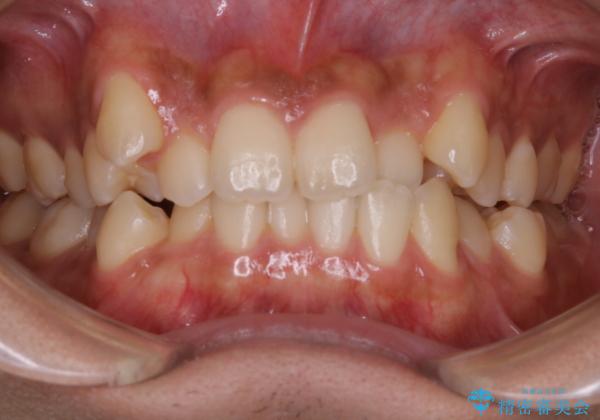

インビザライン単独でここまでできる!!抜歯矯正

1日20時間以上、正しくインビザラインを使用して頂いたおかげで、ワイヤーに切り替えることなく矯正治療を終了することが出来ました。周囲からも歯並びがすごく綺麗になったと言われたのことで大変ご満足いただけました。